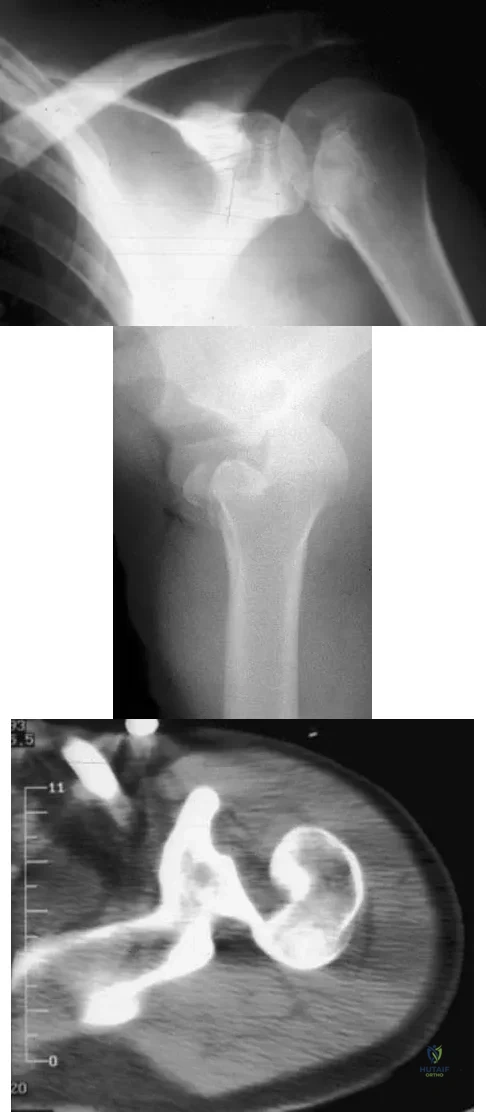

Question 27 High Yield

A 21-year-old patient has had pain and a marked decrease in active and passive shoulder motion after having had a seizure 2 months ago as the result of alcohol abuse. Current AP and axillary radiographs and a CT scan are shown in Figures 26a through 26c. Management should consist of

Detailed Explanation